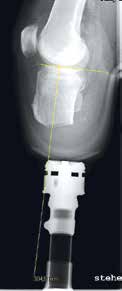

- Die Erstversorgung, besonders nach einer Unterschenkelamputation, sollte mit einem Weichwandinnenschaft vorgenommen werden, da somit bis zur definitiven Versorgung eine bessere Abstützung der dorsalen Weichteile stattfindet. Das bedeutet aber auch, dass zwei Techniker den Gipsabdruck vornehmen müssen: Ein Techniker wickelt, der andere hebt mit einer der Stumpfform angepassten Handfläche den dorsalen Haut-Muskel-Lappen an, damit später der Schaft eine abstützende Funktion ausüben kann.